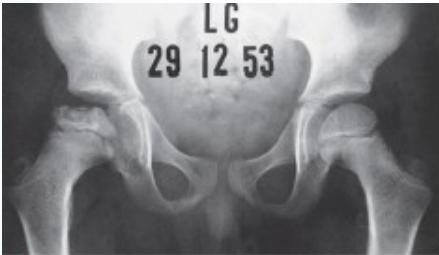

Imaging:

- Required views: AP and Frog lateral pelvis

- Key finding: Slippage of femoral epiphysis

Radiographic Examples:

Comparative views showing slipped vs. normal hip:

(Source: Apley’s System of Orthopedics and Fractures)

X-ray Diagnosis:

| View | Slipped Hip | Normal Hip |

|---|---|---|

| AP | ![]() | - |

| Frog Lateral | ![]() | - |